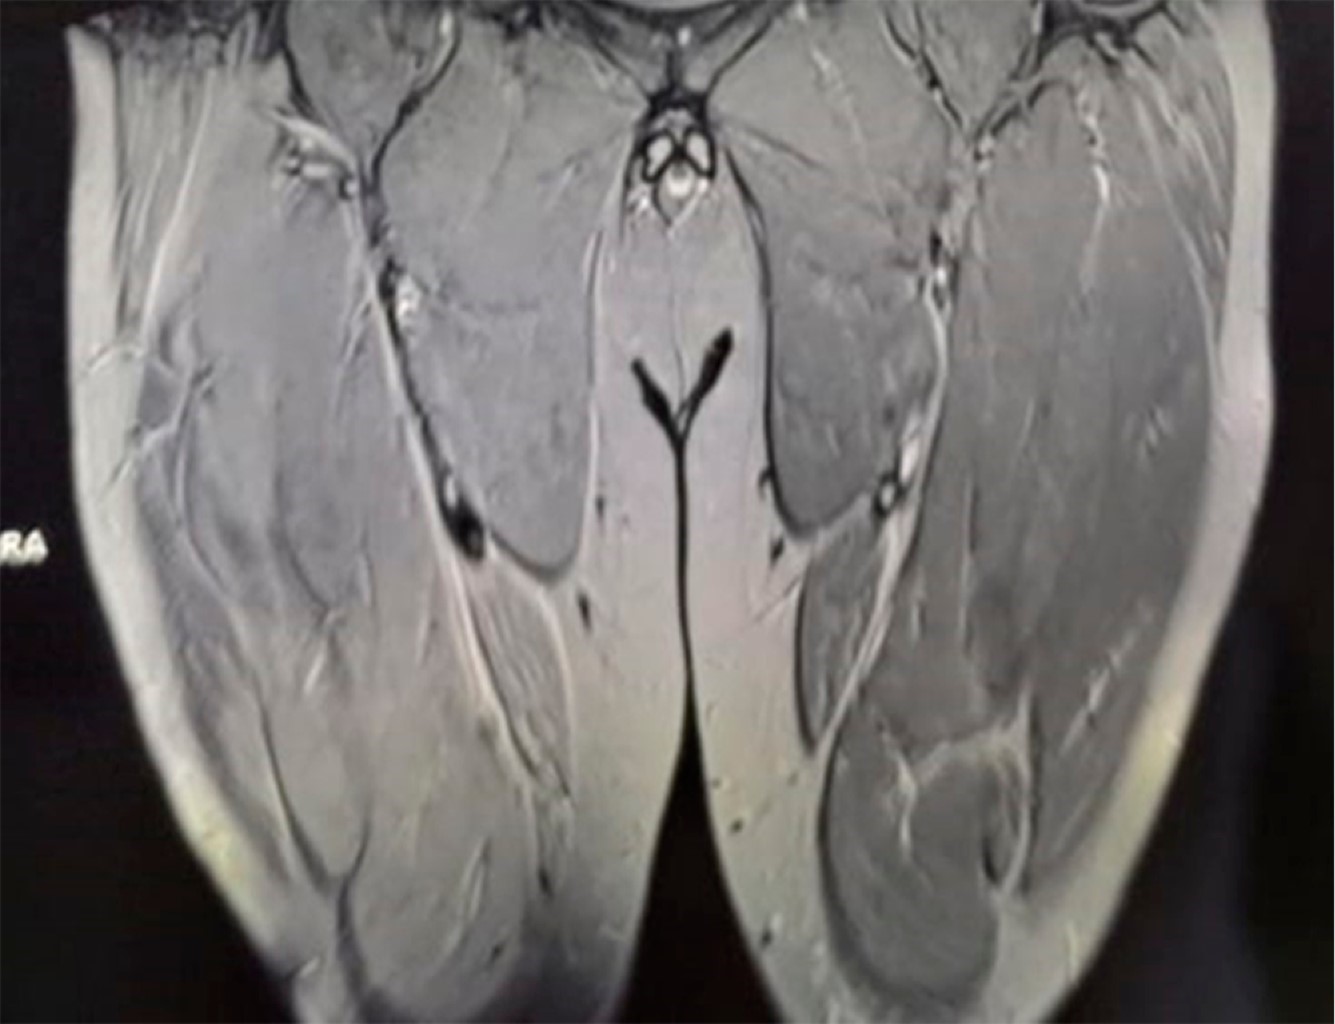

Masculino de 42 años quien realizó ejercicio intenso por 80 minutos, 24 horas después presentó tumefacción dolorosa en cara anterior de ambos muslos, especialmente el derecho con aumento de volumen; incapacidad para la ambulación por dolor en muslos, además de orina oscura. Con diagnóstico presuncional de rabdomiólisis postejercicio. El laboratorio mostró: creatina cinasa (CPK) 11,000 U/L; transaminasa glutámico-oxalacética (TGO) 1,600 U/L; transaminasa glutámico-pirúvica (TGP) 280 U/L; el examen general de orina (EGO) oscura sin hematíes. La resonancia magnética (RM) mostró edema muscular de predominio derecho en cuádriceps y disrupción parcial de fibras del recto anterior (Figura 1).

La rabdomiólisis se caracteriza por necrosis de las células musculares, liberación de mioglobina, proteínas sarcoplásmicas y elevación de enzimas (CPK, LDH, TGO y TGP). En la patogenia indica lesión del sarcolema y/o depleción de adenosín trifosfato (ATP) en el miocito, destrucción muscular por aumento de calcio intracelular y contracción muscular persistente, disfunción mitocondrial, producción de radicales libres de oxígeno y activación de proteasas. La RM es de elección para diagnóstico, el edema es el patrón de anormalidad muscular observado con mayor intensidad de señal en imágenes potenciadas en T2 o STIR. El edema simétrico es típico de las miopatías inflamatorias y relacionadas con fármacos, el asimétrico corresponde a infección, radiación, mionecrosis y síndrome compartimental.

Figura 1